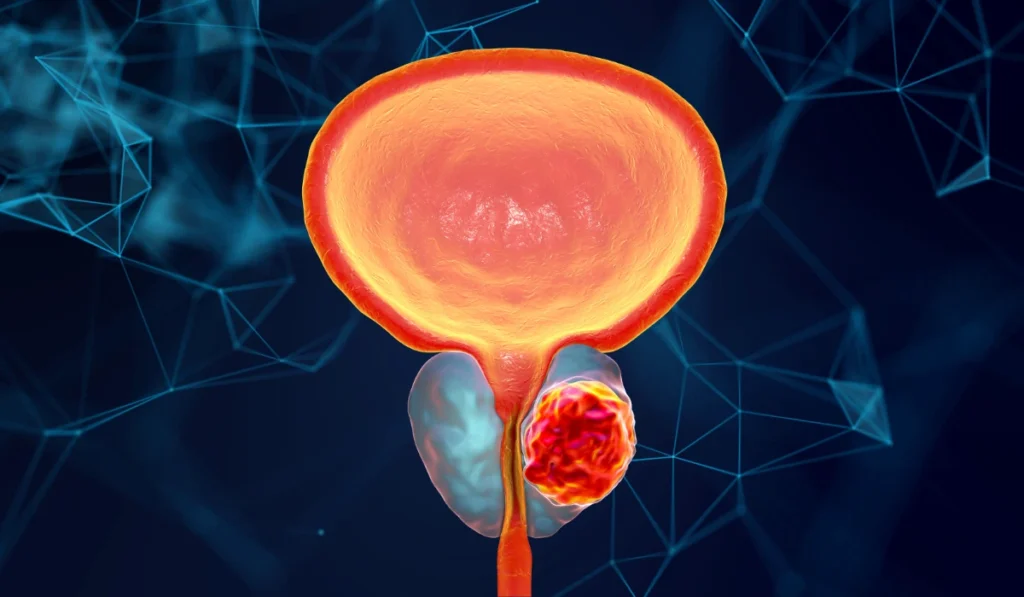

Memahami Risiko Pembengkakan Prostat Jinak atau BPH

Kondisi Benign Prostatic Hyperplasia atau BPH terjadi saat kelenjar prostat mengalami pembesaran secara non-kanker. Hal ini mengakibatkan aliran urine menjadi terhambat dan memicu rasa tidak nyaman saat sedang beraktivitas.

Tekanan pada kandung kemih membuat frekuensi buang air kecil meningkat secara drastis terutama malam hari. Gejala ini sering mengganggu waktu istirahat dan menurunkan produktivitas kerja bagi para pria dewasa produktif.